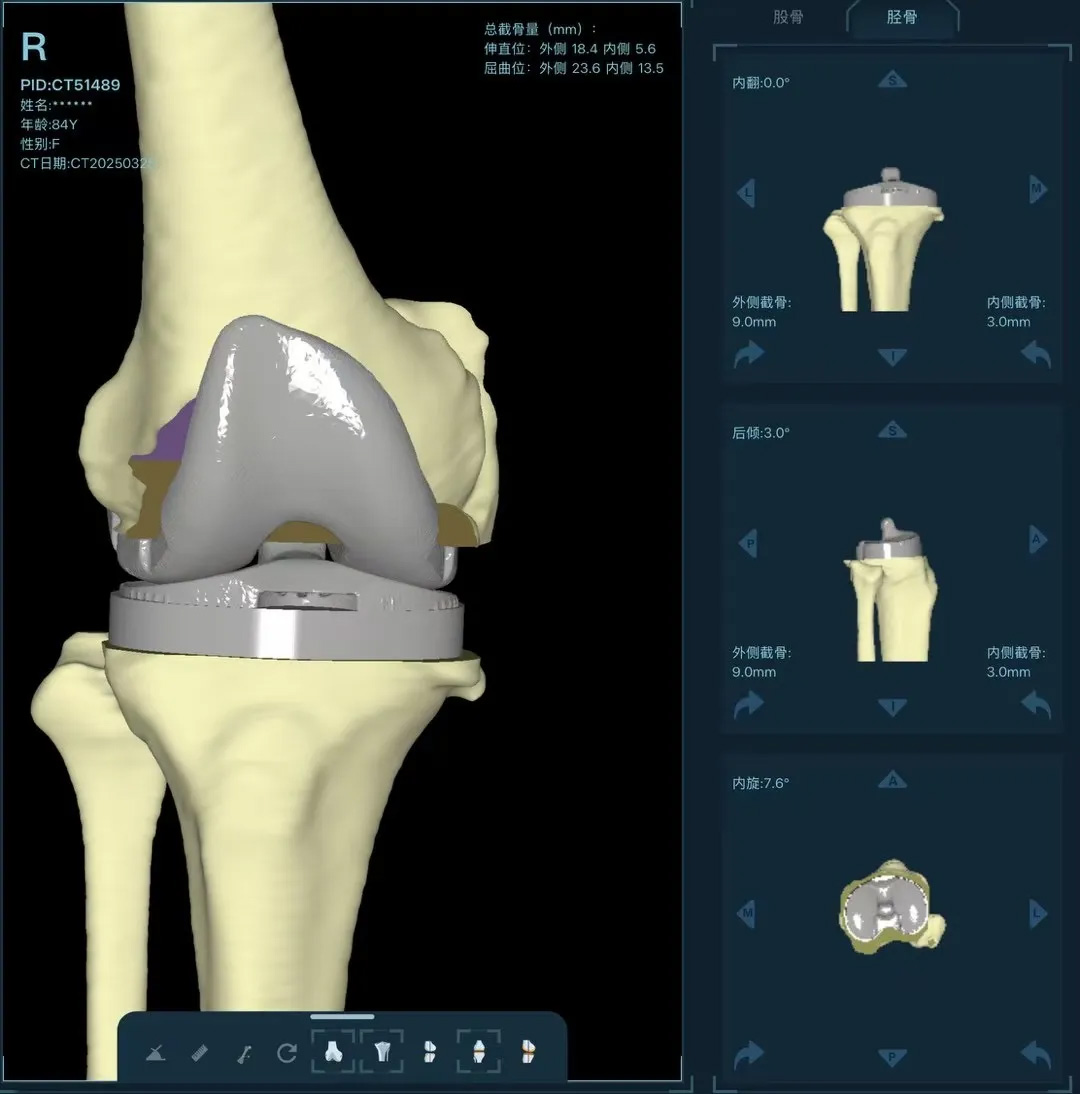

在家人幾乎放棄希望時(shí),AI三維規(guī)劃技術(shù)為這場(chǎng)"關(guān)節(jié)保衛(wèi)戰(zhàn)"帶來轉(zhuǎn)機(jī)。

術(shù)前:AI通過CT掃描生成毫米級(jí)膝關(guān)節(jié)三維模型,為假體安裝設(shè)計(jì)出誤差小于1毫米的精準(zhǔn)方案 術(shù)中:智能導(dǎo)航系統(tǒng)如同"透視眼",引導(dǎo)醫(yī)生避開密集的神經(jīng)血管網(wǎng),截骨更精準(zhǔn),出血僅100ml 術(shù)后:當(dāng)天鄭阿婆即開始抬腿的康復(fù)訓(xùn)練,24小時(shí)內(nèi)扶助行器下地行走,三天后已能在病房走廊獨(dú)立行走,完成洗漱用餐 兩周后健步出院時(shí),女兒含淚感慨“之前擔(dān)心她年紀(jì)大扛不住手術(shù),沒想到恢復(fù)這么快!現(xiàn)在每天散步比我還精神。知道技術(shù)這么先進(jìn),真該早點(diǎn)來!”

"這就像給傳統(tǒng)手術(shù)裝上了自動(dòng)駕駛系統(tǒng)。"主刀醫(yī)生羅軍副院長(zhǎng)用生動(dòng)比喻解析技術(shù)突破。AI不僅實(shí)現(xiàn)假體“量身定制”,使用壽命可達(dá)20年以上,更通過三維路徑規(guī)劃將康復(fù)周期壓縮,實(shí)現(xiàn)術(shù)后24小時(shí)下地,2周回歸正常生活。同時(shí),AI會(huì)避開重要組織,具有出血少、感染風(fēng)險(xiǎn)低的特點(diǎn)。專家特別提醒,當(dāng)出現(xiàn)夜間持續(xù)性關(guān)節(jié)疼痛、步行能力低于10分鐘或關(guān)節(jié)畸形時(shí),應(yīng)及時(shí)就醫(yī)評(píng)估,"別等到關(guān)節(jié)'報(bào)廢'才手術(shù)"。